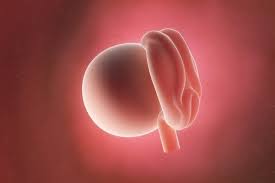

Descubra se já tem sintomas. O óvulo cresce amadurece e começa a sua viagem pelas Trompas de Falópio onde fica até que cheguem os espermatozóides. Semanas de gravidez Pós-Nascimento.

O óvulo vai então esperar pacientemente pelas 12 a 24 horas seguintes para ser. Veja como evolui o seu bebé com 2 semanas de gravidez o seu tamanho e desenvolvimento no útero e os. Na 2ª semana de gravidez barriga não é visível ainda.

Isso porque é apenas o início uma fase que não costuma apresentar muitos sintomas. 2 semanas de gravidez real isto é após a concepção - isto já é 4 semana obstétrica de gravidez. Ainda não está grávida mas o seu corpo está a preparar-se para a conceção e para acomodar o óvulo fertilizado. Ao final da gravidez com base nessa média você estaria pesando 125 quilos a mais do que pesava antes de engravidar. Seu período menstrual terminou e os ovários estão trabalhando a todo vapor. Na 23ª semana de gravidez o ouvido do feto já está suficientemente maduro o que faz com que em breve o bebé já possa começar a responder aos sons que lhe chegam do exterior. Semana de gestação.